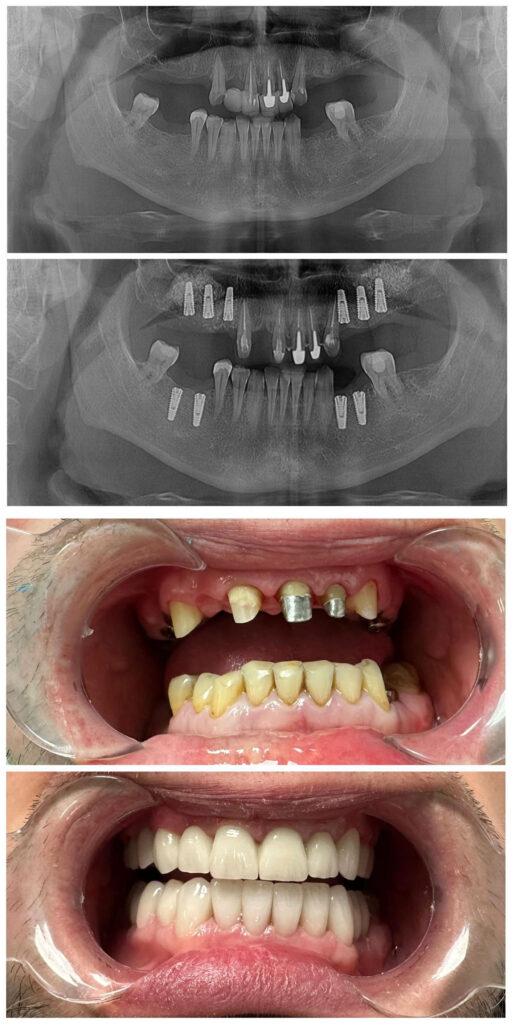

Caz de reabilitare a întregi cavități orale:

s-au aplicat implanturi dentare Megagen în spațiile edentate urmate de coroane zirconiu-ceramice înșurubate

superior o lucrare fixă zirconiu-ceramică

inferior fațete dentare